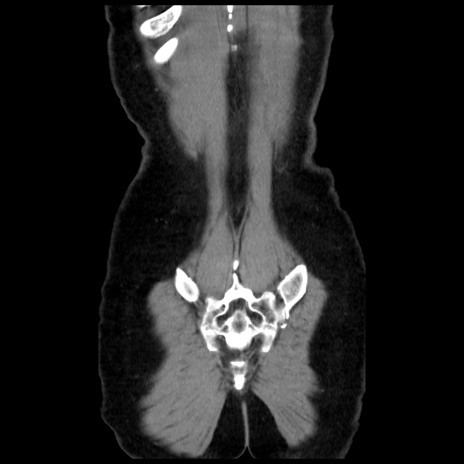

矢状断像